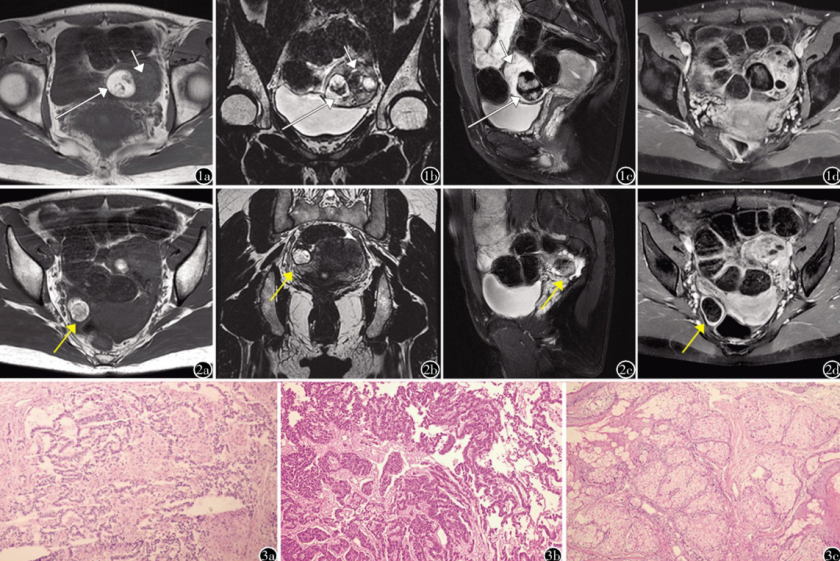

左侧卵巢成熟囊性畸胎瘤和Sertoli-Leydig细胞瘤构成的卵巢碰撞瘤。图1 a)盆腔MR轴位T1WI平扫:左侧附件区见一实性为主肿块,内含两个部分,偏外上份部分以实性为主,信号不均匀,T1WI呈等、稍低信号(短箭 );偏内下份另见一含脂肪混杂信号结节,呈类圆形,界限清楚,边缘光整;b)冠状位MRT2WI平扫:肿块外上份T2WI呈高、低混杂信号(短箭),内见小囊变区;内下份含脂结节T2WI呈高低混杂信号(长箭);c)矢状位MRT2WI压脂:肿块外上份T2WI压脂呈等、高混杂信号(短箭);内下份含脂结节T2WI压脂外周信号明显减低(长箭);d)轴位MRT1WI增强:增强扫描肿块实性成分及部分囊壁可见显著强化,囊内容物及含脂结节未见强化。图2 a)盆腔 MR轴位T1WI平扫、b)冠状位MRT2WI平扫、c)矢状位 MRT2WI压脂、d)轴位 MRlT1WI增强,右侧附件区见一类圆形囊实性肿块,边界清晰,信号欠均匀,各序列均呈高低混杂信号,局部可见 T2WI高信号,T2WI脂肪抑制序列低信号的脂肪成分,增强扫描囊性成分和脂肪成分未见明显强化(箭)。图3 左侧附件区肿块病理图(HE,xl00)a)肿块偏外上份部分显微镜下可见呈条索状排列的不成熟Sertoli细胞及b)含有丰富胞质的Leydig细胞呈簇状排列;c)偏内下份含脂结节镜下见皮肤组织及脂肪组织等杂乱无章排列。